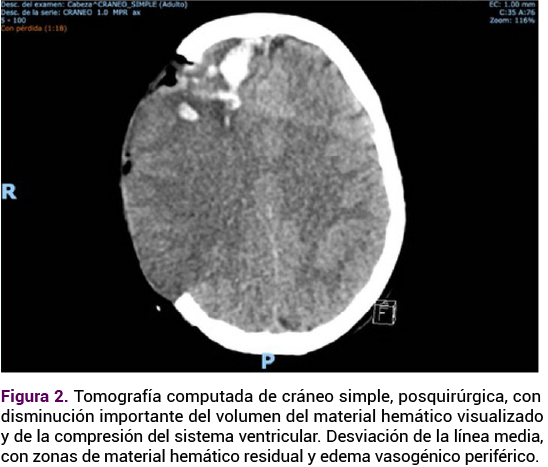

Se indicaron 200 mg de progesterona intravaginal cada 24 horas, vigilancia con toalla testigo y ultrasonido obstétrico de control. En la TAC de control posquirúrgico se apreció mejoría, con disminución del volumen del material hemático visualizado. Se indicaron: vigilancia neurológica y diuresis, antibiótico profiláctico y tromboprofilaxis con vendas de compresión neumática intermitente.

<strong>Figura 2</strong>

Figura 2. TAC de control posquirúrgico. Mejoría, con disminución del volumen del material hemático visualizado.